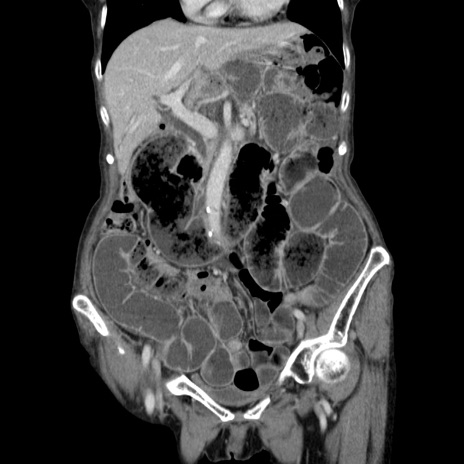

症例25(冠状断像)

【症例】80歳代女性

【現病歴】約9時間前に食後から胸のつかえた感じあり、嘔吐あり、来院。

【既往歴】胃癌(全摘)、胆摘、虫垂炎